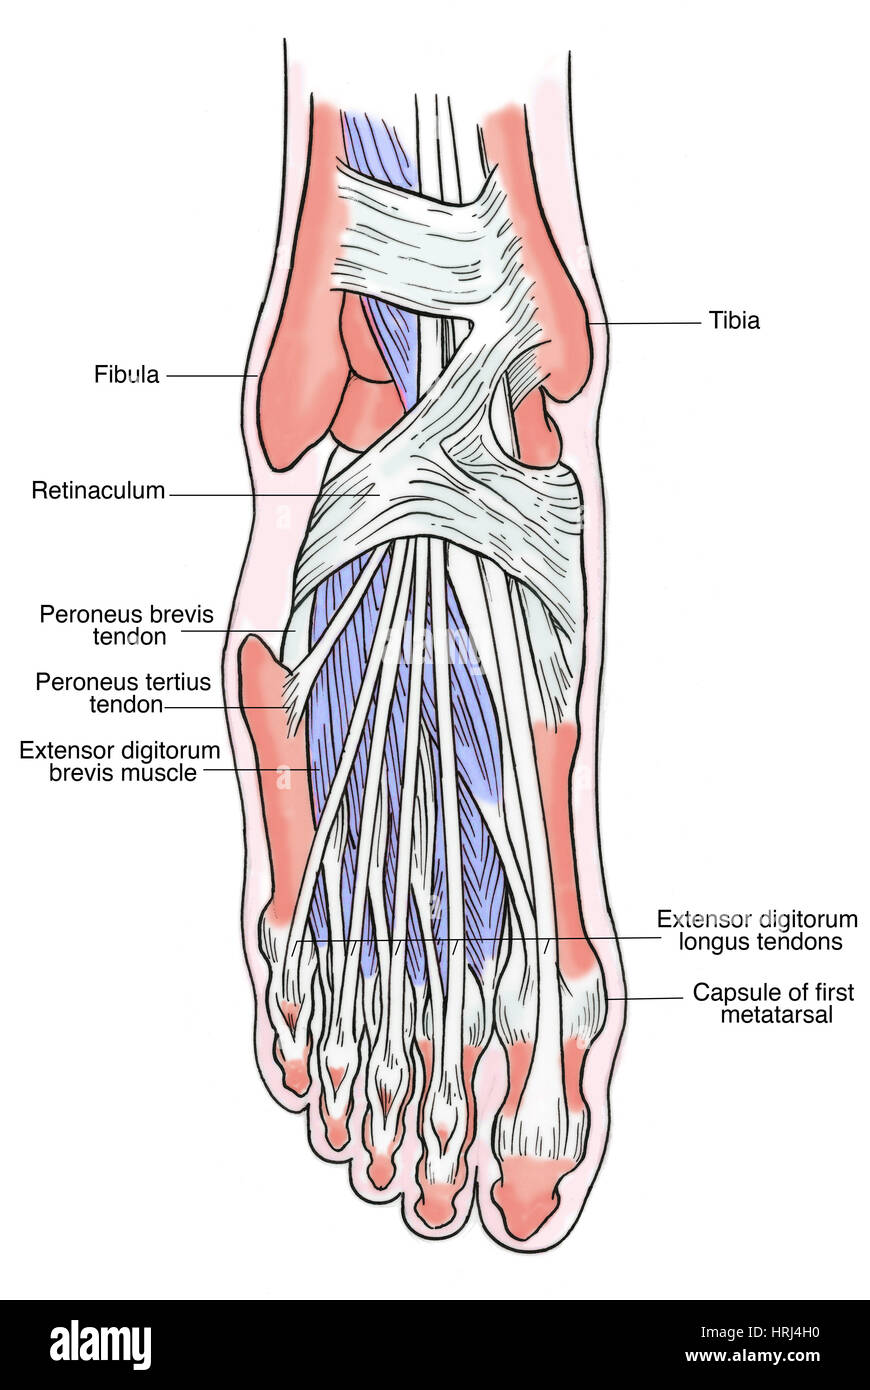

it.dreamstime.comL’anatomia Muscolare Del Piede Illustrazione Di Stock - Illustrazione

it.dreamstime.comL’anatomia Muscolare Del Piede Illustrazione Di Stock - Illustrazione

it.dreamstime.compiede anatomia muscolare umano

it.dreamstime.compiede anatomia muscolare umano

cartoondealer.comIl Piede Umano Muscles L’anatomia Illustrazione Di Stock

cartoondealer.comIl Piede Umano Muscles L’anatomia Illustrazione Di Stock

it.dreamstime.commuscles anatomie pied piede humain anatomy anatomia umano menselijke medicamente cuboid ligament

it.dreamstime.commuscles anatomie pied piede humain anatomy anatomia umano menselijke medicamente cuboid ligament